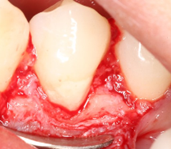

Procedure Photos

Removed granulation tissue